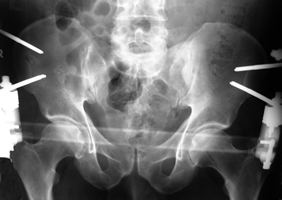

Vordere und hintere Beckenringfraktur bei Polytrauma. Hier ist die Stabilisierung mit Fixateur allein nicht stabil genug. In einem solchen Fall sollte zuerst die hintere Fraktur mit Platte, Schrauben oder wie in diesem Fall mit mit einer Drahtgurtung stabilisiert werden. Danach wird der Patient in Rückenlage gebracht und der Beckenring vorne mit einem Fixateur befestigt. Belastung ist meist nach 4-5 Wochen möglich.